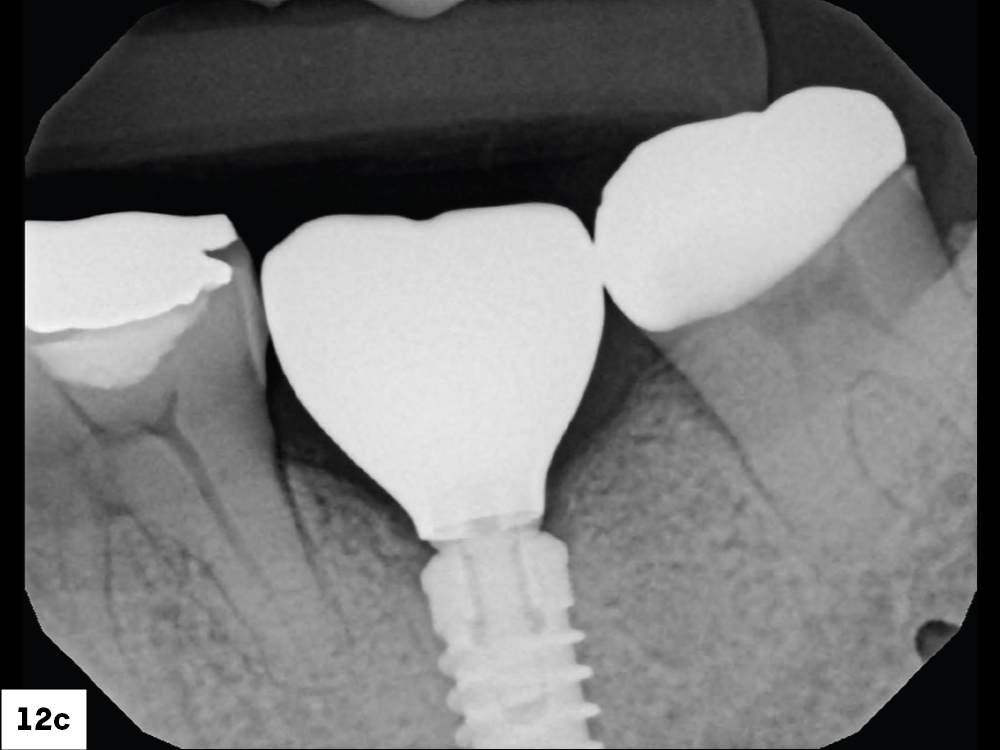

BruxZir NOW SRC in mouth with open access channel

BruxZir NOW SRC in mouth with closed access channel

BruxZir NOW SRC in mouth radiograph

Figures 12a–12c: The screw-retained crown was seated and the access channel sealed with Teflon tape and composite. The final restoration showed ideal contacts, occlusion and emergence profile.